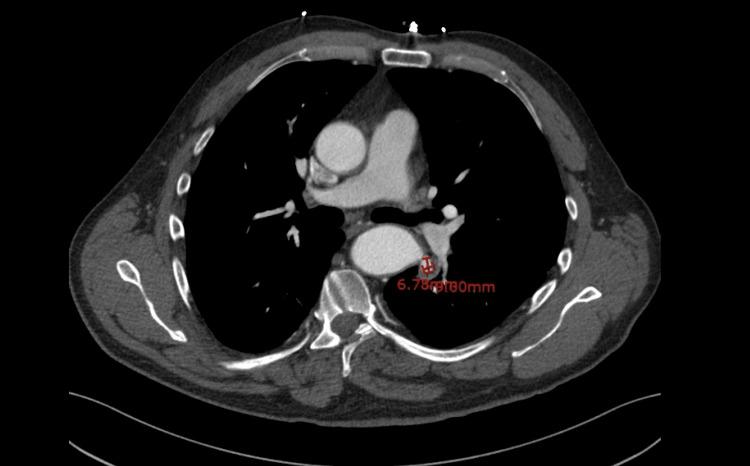

"Hemoptysis" refers to the expectoration of blood from the respiratory tract. However, "life-threatening hemoptysis" includes any volume that leads to features such as airway obstruction, hypoxia, or hemodynamic instability. We present a case of life-threatening hemoptysis in a 65-year-old male with a history of benign prostatic hyperplasia and uncontrolled hypertension. Radiological investigations revealed a pseudo-aneurysm at the site of a prior thoracic aortic coarctation repair more than 50 years prior in childhood. He required vascular surgical intervention, during which there was evidence of an aorta-bronchial fistula as the likely cause of bleeding. Following the repair and optimal blood pressure control, the patient had no further episodes of hemoptysis and was discharged from the hospital. His case not only adds to the growing body of medical literature reporting hemoptysis as a complication of coarctation repair but also highlights the aorto-bronchial fistula as a possible and potentially catastrophic mechanism for bleeding in these patients.

“咯血”指呼吸道出血并咳出。然而,“危及生命的咯血”包括导致气道阻塞、缺氧或血流动力学不稳定等特征的任何出血量。我们报告一例65岁男性危及生命的咯血病例,该患者有良性前列腺增生和未控制的高血压病史。影像学检查显示,患者童年时期(50多年前)曾行胸主动脉缩窄修复术,目前修复部位存在假性动脉瘤。他需要进行血管外科干预,术中发现主动脉-支气管瘘可能是出血原因。修复术后并实现最佳血压控制后,患者未再发生咯血并出院。他的病例不仅增加了将咯血作为缩窄修复并发症报告的医学文献数量,还突出了主动脉-支气管瘘作为这些患者出血的一种可能且潜在灾难性机制。